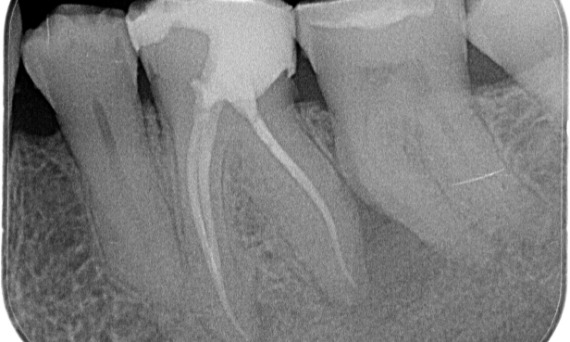

"Elegí TruNatomy para poder conservar la mayor cantidad de dentina posible y superar la carga oclusal y aumentar la longevidad del diente". - Dr. Abuelezz

Antes: Tras el examen, hubo una lesión de caries relacionada con el primer molar inferior derecho. El examen radiográfico reveló la proximidad de la lesión a la bocina pulpar y, al combinarla con la queja principal, se concluyó un diagnóstico final de pulpitis irreversible crónica.

Después: La cavidad de acceso se realizó de la manera más conservadora posible. TruNatomy fue el sistema de elección debido a la edad del paciente joven. Necesitábamos preservar la dentina tanto como fuera posible para aumentar la capacidad del diente y así superar la carga oclusal y aumentar la longevidad de la restauración final.

Dr. Ahmed Hussein Abuelezz (PHD en endodoncia)

El Cairo, Egipto